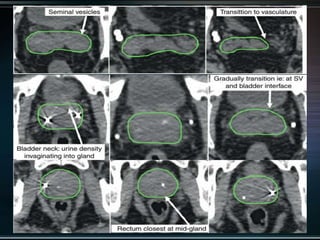

Delineation

Our unit decide to treat:

 Prostate + S.V & prophylactic Pelvic LNs in

phase1

 Prostate + S.V phase 2

 Delineation of our unit illustrated in the

following slides:

Our unit decideto treat:  Prostate + S.V & prophylactic Pelvic LNs in phase1  Prostate + S.V phase 2  Delineation of our unit illustrated in the following slides: